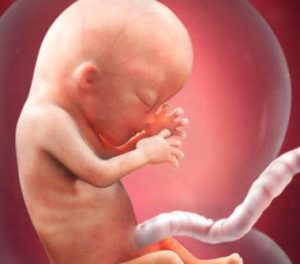

Karnınızdaki bebeğinizin ikinci üç aylık dönemi başlıyor. Hamileliğinizin 13. haftasında bebeğinizin boyu 6.5 ila 10 santimetreye, ağırlığı ise 13 ila 20 grama ulaşır.

Aşağıda bahsedeceğimiz birçok oluşumun yanı sıra bebeğinizin yüzü de şekillenmeye başlar. Son derece heyecan verici değil mi!

Kulaklarının ve gözlerinin son şeklini alması ile birlikte bebeğinizin parmak izleri de bu dönemde oluşur.

Hamileliğin bu evresinde iç organları koruyan ve kaplayan yapı ile birlikte fetüsün en çok gelişen bölümlerinden biri de beyindir.

Hamileliğinizin on üçüncü haftasında fetüsün kafası toplam boyutun yarısını oluşturur.

Bu noktadan sonra fetüsün gövdesi gelişim hızını arttırıp kafa kısmı ile birlikte orantılı bir görünüme kavuşacaktır.

Aslına bakarsanız bebeğiniz doğduğunda kafası tüm boyutunun sadece dörtte birini oluşturuyor olacaktır. Tüm bu gelişimlere ek olarak fetüsün vücudu ve bu vücudun işleyişi ile ilgili bir-iki önemli süreç daha vardır.